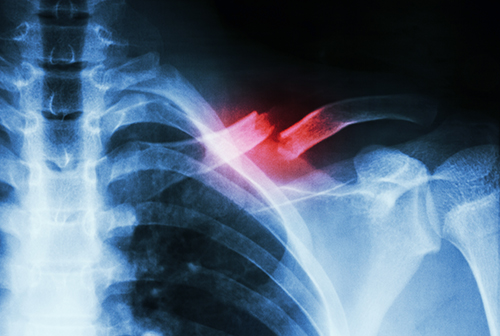

Landmark Study Finds Antisepsis Agents Interchangeable in Reducing Infection Risk in Open Fracture Surgeries

Orthopaedics faculty at LSU Health New Orleans participated in a study comparing two antisepsis aqueous solutions in reducing the risk of infection in patients requiring surgery for open fractures. In the largest known randomized-controlled trial, the research team found that contrary to current international recommendations, chlorhexidine gluconate was not superior to povidone-iodine in an alcohol or aqueous solution in preventing surgical site infection. More